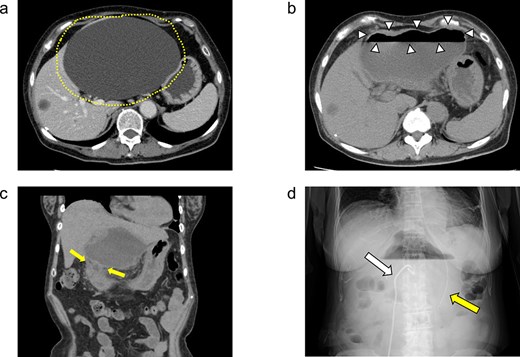

On day 13 of admission, an upper gastrointestinal contrast examination showed no obvious communication between the hepatic cyst and the duodenum (Fig. 2a). On day 20, CT showed that the hepatic cyst had tended to shrink but had not disappeared; in addition, the cyst wall had thickened (Fig. 2b). The CT also identified a low-density area between the hepatic cyst and the duodenum, which we suspected was a fistulous tract between them (Fig. 2c). On day 21, an upper gastrointestinal endoscopy revealed an ulcer scar at the anterior aspect of the duodenum bulb (Fig. 2d). A biopsy of the ulcer scar tissue revealed no malignancy.

The upper gastrointestinal contrast examination findings on day 13 of the patient’s hospital admission. (a) There was no obvious fistulous tract between the hepatic cyst and the duodenum. arrowheads: The stomach, arrowheads: The duodenum. arrow: The 7Fr pig-tail catheter. (b, c) Enhanced CT images findings on 20 day of admission. (b) Axial section. A shrunken hepatic cyst with a thickened cyst wall was observed. Dotted line: The large hepatic cyst. Arrowheads: The 7Fr pig-tail catheter. (c) Coronal section. A a low-density area was observed between the hepatic cyst and the duodenum, suspected of being a fistulous tract. Arrows: The low-density area between the hepatic cyst and the duodenum. Arrowheads: The 7Fr pig-tail catheter. (d) An upper gastrointestinal endoscopy on admission day 21 showed an ulcer scar at the anterior aspect of the duodenum bulb without obvious fistulous orifice. Arrowheads: The ulcer scar at the anterior aspect of the duodenum bulb.